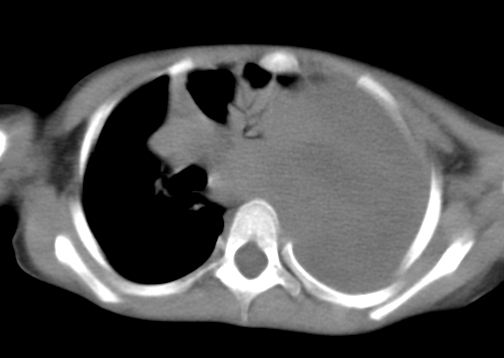

患儿 女 4岁,发热 咳嗽 胸透 考虑:左侧脓胸

左侧胸廓内见大量密实阴影,肺尖部尚有少量肺组织影,纵膈明显受压移位,肋骨未见明显受侵征象,虽然病人年龄较小,但如此大量的“积液”,还是要警惕,不同意一般感染,可结合穿刺脱落细胞学检查。

1)考虑左肺炎症感染。2)左侧大量胸腔积液。

左侧张力性大量胸腔积液压迫性肺不张、感染;建议治疗后复查。